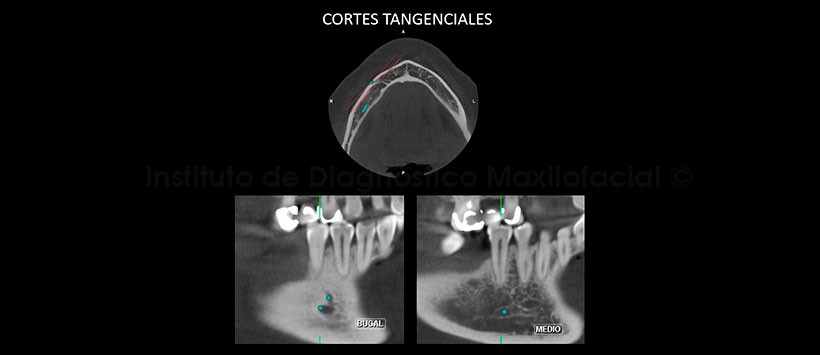

La tomografía computarizada de haz cónico, mediante los cortes transaxiales y tangenciales, muestra claramente la presencia de dos agujeros mentonianos en un mismo lado, en este caso en la parasínfisis mandibular del lado derecho; además, de su distribución a nivel de la tabla ósea bucal (Fig. 2 y 3).